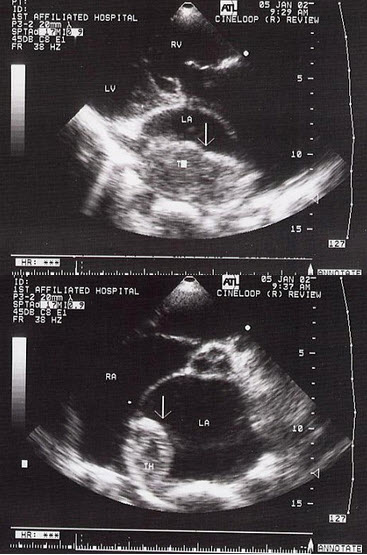

30、单项选择题

根据心尖四腔切面声像图所示,超声诊断为()

A.右房血栓

B.三尖瓣赘生物

C.右房黏液瘤

D.正常声像图

E.二尖瓣脱垂